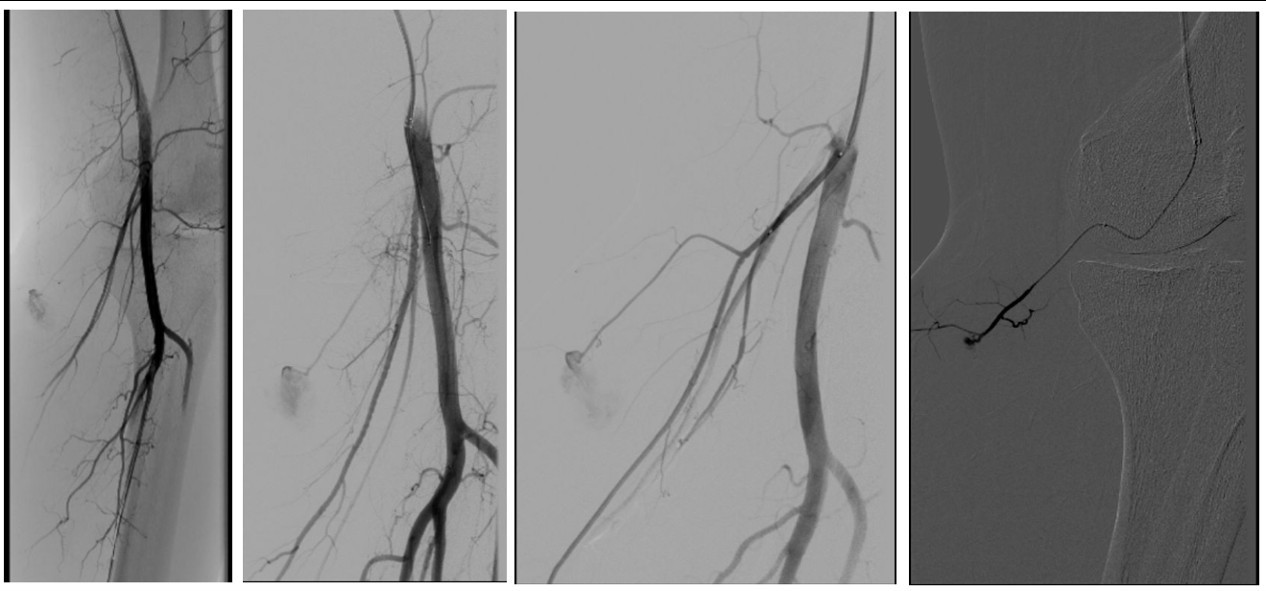

Inmediatamente finalizada la embolización en hemodinamia, el paciente fue trasladado a quirófano donde, bajo anestesia general, se realizaron tres incisiones para efectuar la fasciotomía con descompresión de los cuatro compartimentos de la pierna.

Se evacuó extenso hematoma ubicado entre la fascia medial del gemelo interno y en el plano profundo del sóleo, lo que generó una pronta mejoría clínica (Fig. 5).

Tras la descompresión, se logró palpar nuevamente pulso en la arteria dorsal del pie.

Figura 4. Embolización selectiva de la rama genicular de arteria poplítea